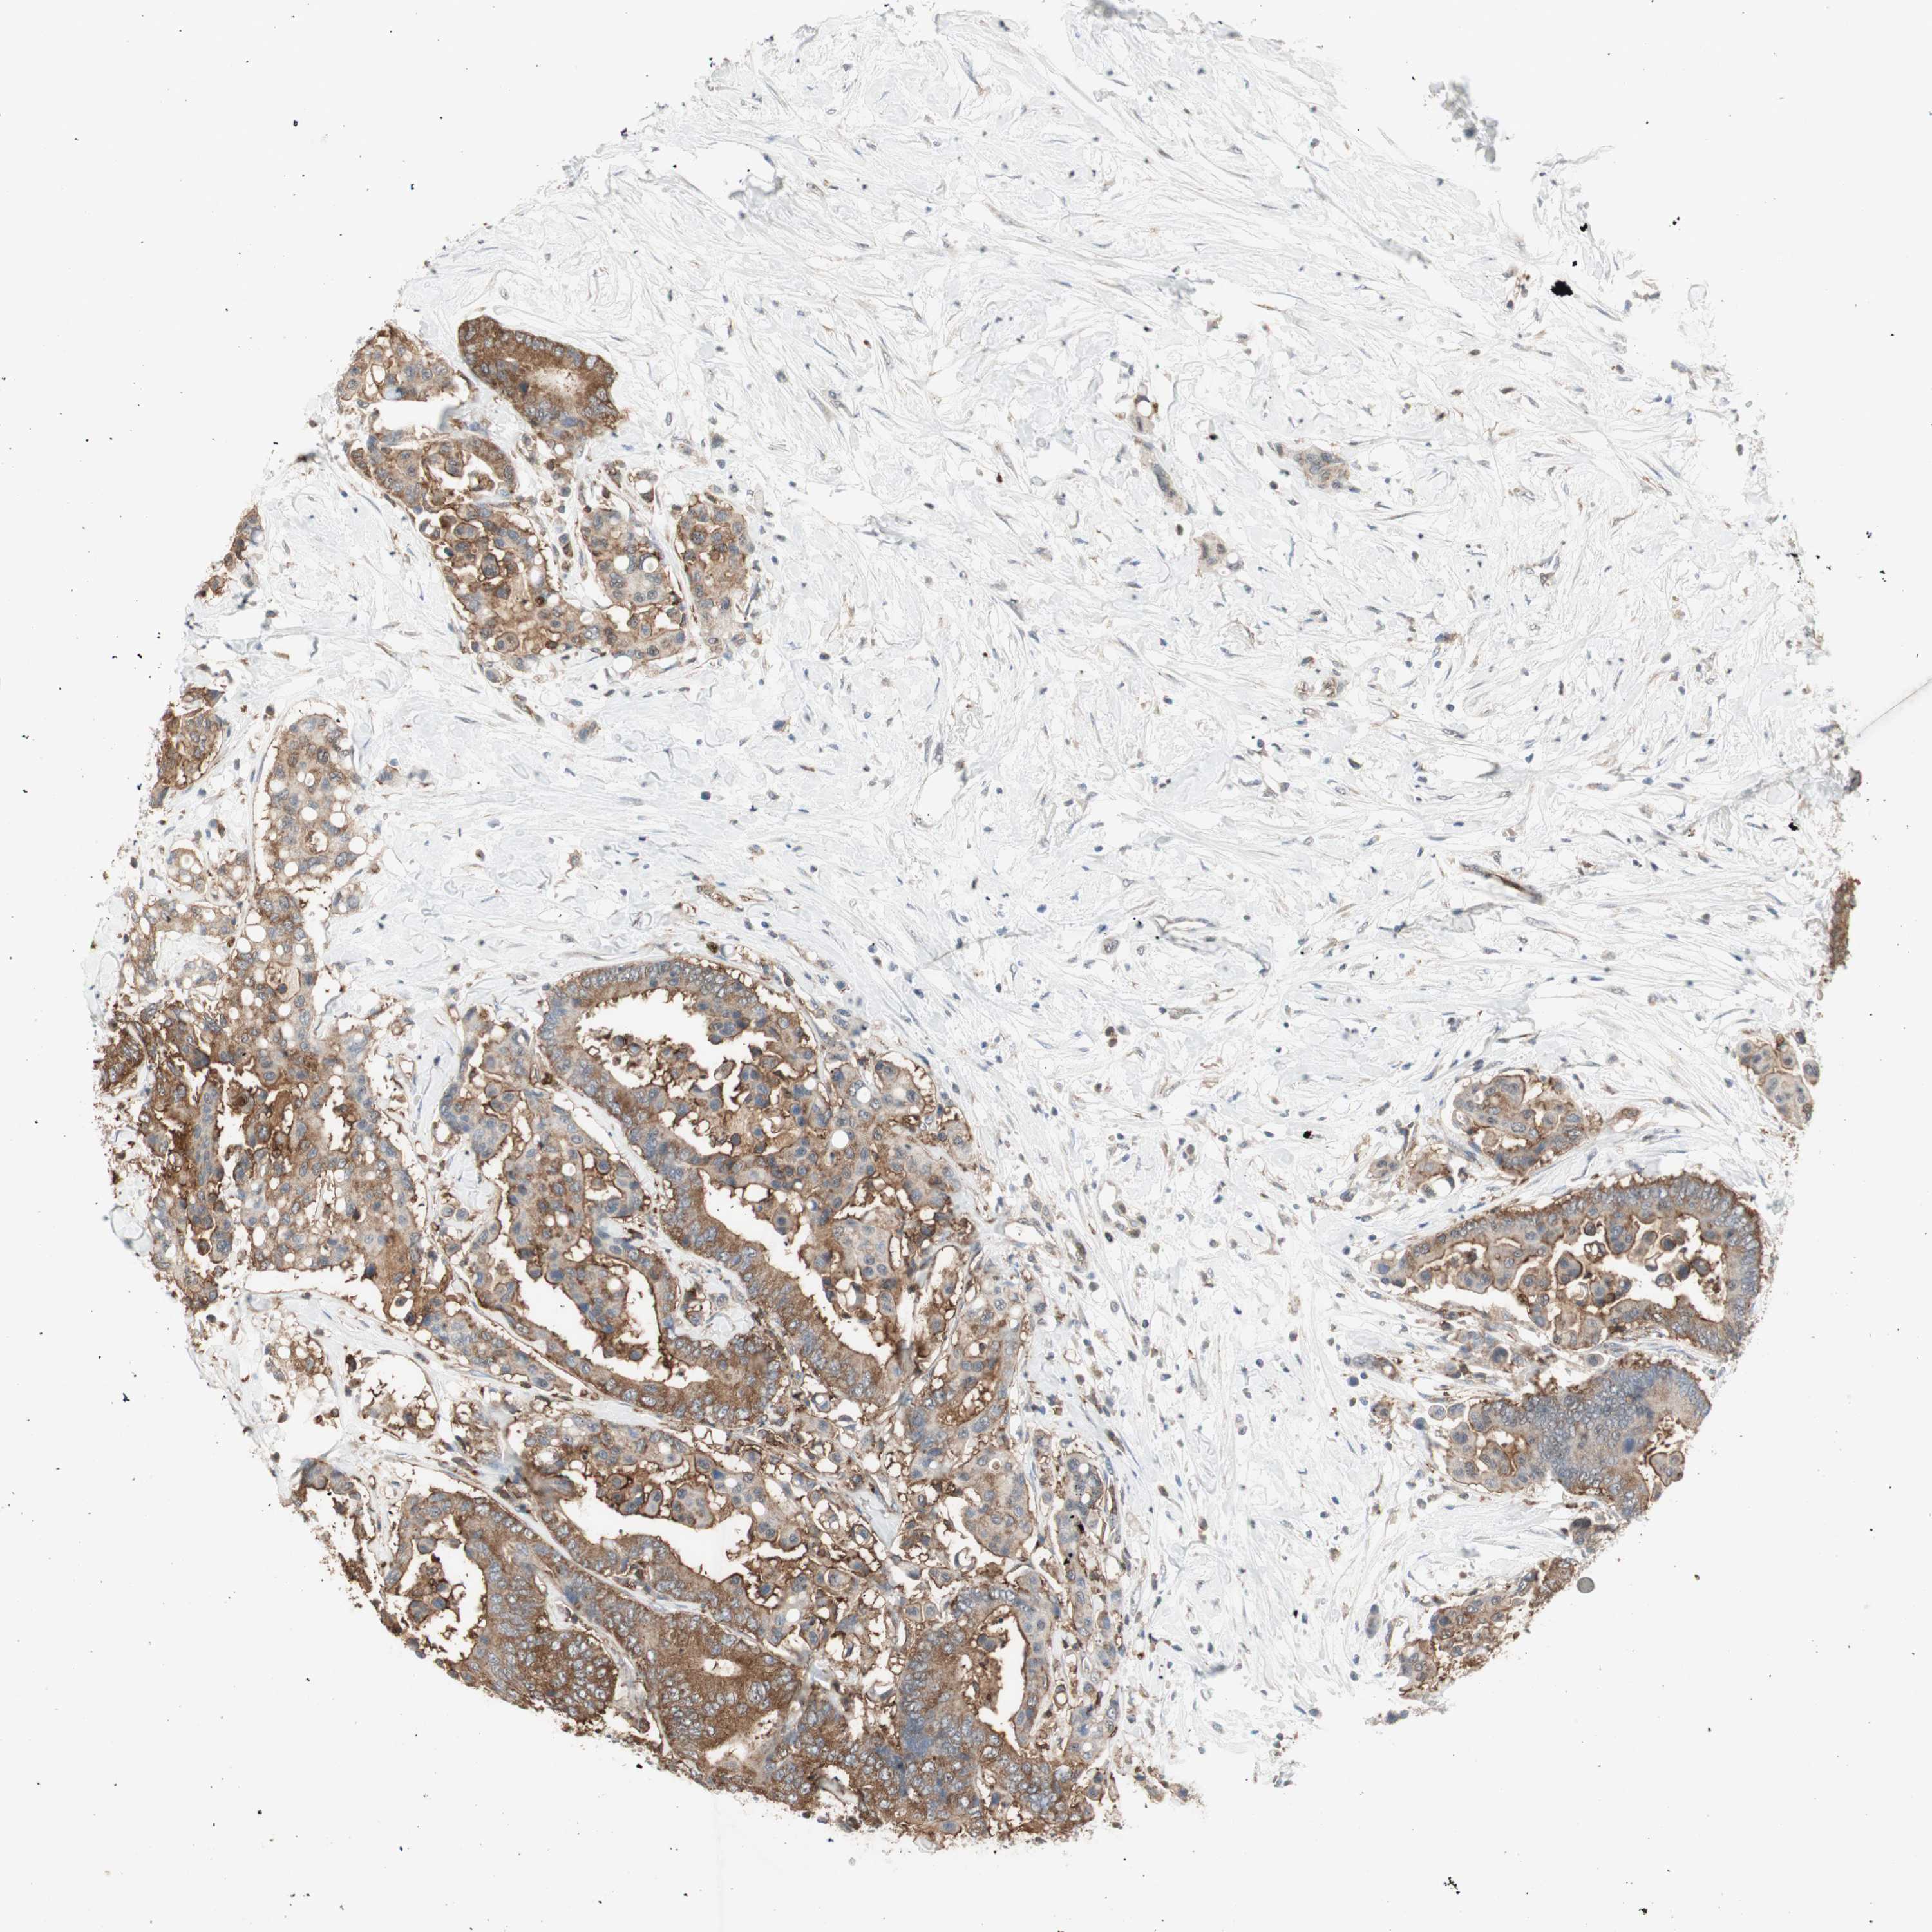

CANCER COLORECTAL CANCER Show tissue menu

Colorectal cancer

Human cancer

Colon adenocarcinoma

Rectum adenocarcinoma